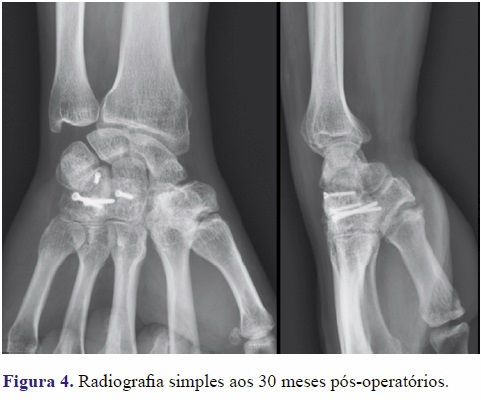

Aos 30 meses de seguimento, o doente apresentava uma boa mobilidade do punho com 65º de flexão, 60º de extensão, 19º de desvio cubital e 20º de desvio radial (Figura 3). Não tinha limitação da amplitude ou queixas álgicas à prono-supinação ou com a execução do “dart-throwing motion”, e a oponência era completa. A radiografia não revelava sinais de osteonecrose do trapezoide ou de qualquer outro osso do carpo (Figura 4).